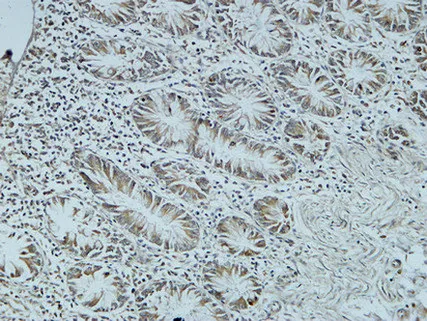

CD19 Rabbit Polyclonal Antibody

Cat: APRab08256

Size1:50μl Price1:$128

Size2:100μl Price2:$230

Size3:500μl Price3:$980

Size2:100μl Price2:$230

Size3:500μl Price3:$980